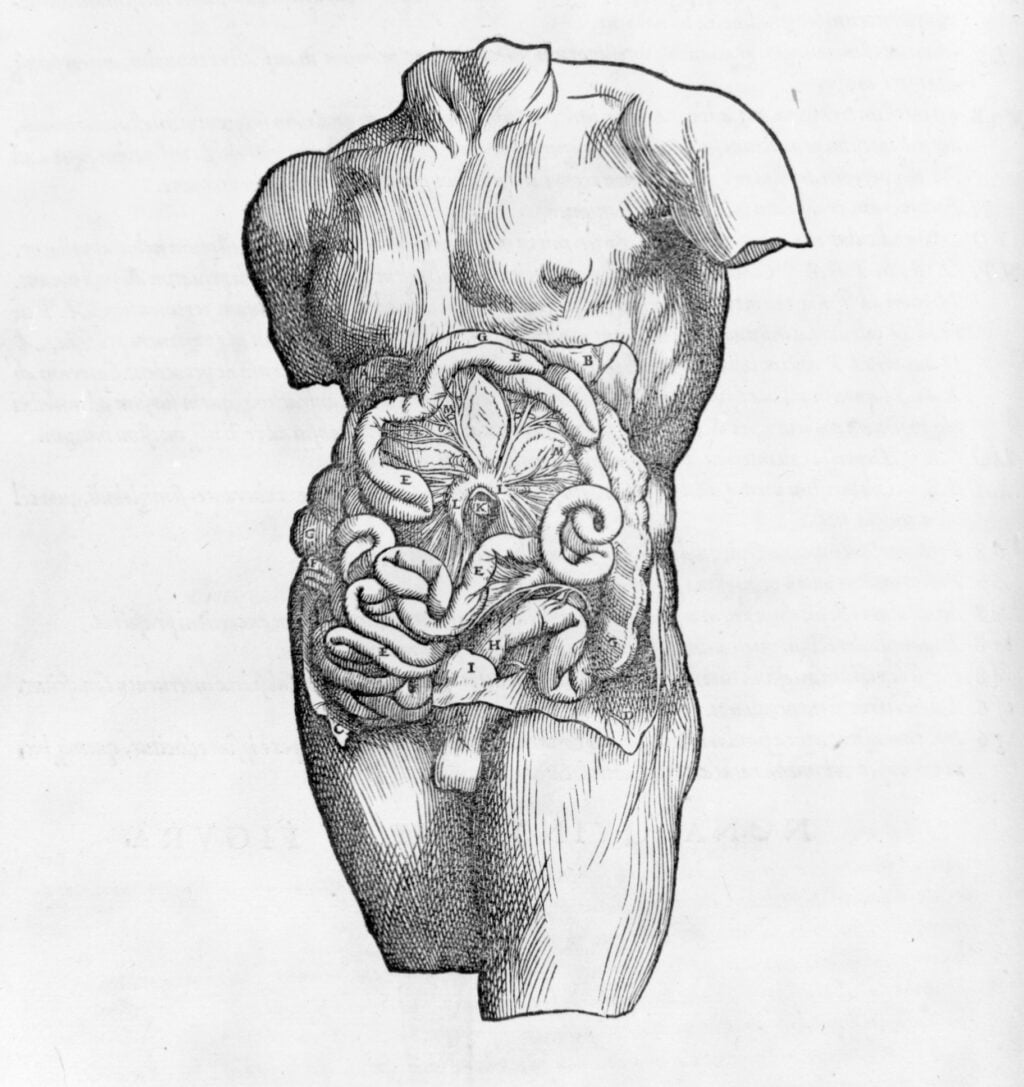

Claro que después de que se rompió con las barreras de la disección en el medioevo europeo, aparecieron publicaciones como el Isagoge breves de Berengario da Carpi (considerado por algunos como el primer anatomista) a la cual seguiría Andreas Vesalius con su De Humani Corporis Fabrica Libri Septum, el cual se convirtió en uno de los libros de mayor influencia en cuanto a anatomía humana se refiere.

De hecho, prácticamente cada fuente que se encuentre sobre dibujar Ilustración Médica hablará sobre los estudios de Vesalius y, por supuesto, de los de Leonardo Da Vinci (sobre quién contamos con una variedad de publicaciones, como la de “El dibujo a la manera de Leonardo da Vinci”).